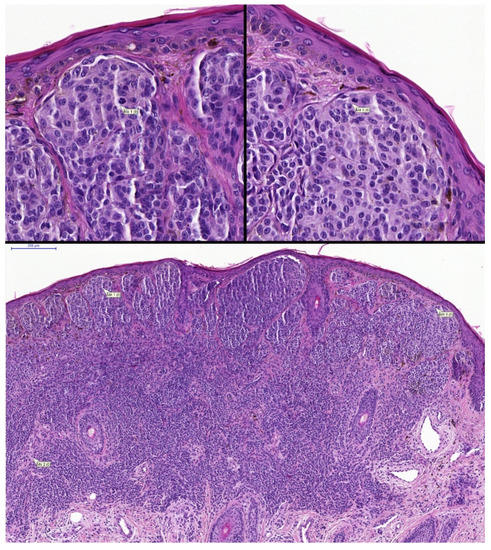

- Andres, C.; Andres-Belloni, B.; Hein, R.; Biedermann, T.; Schape, A.; Brieu, N.; Schonmeyer, R.; Yigitsoy, M.; Ring, J.; Schmidt, G.; et al. iDermatoPath—A novel software tool for mitosis detection in H&E-stained tissue sections of malignant melanoma. J. Eur. Acad. Dermatol. Venereol. 2017, 31, 1137–1147. [Google Scholar] [CrossRef]